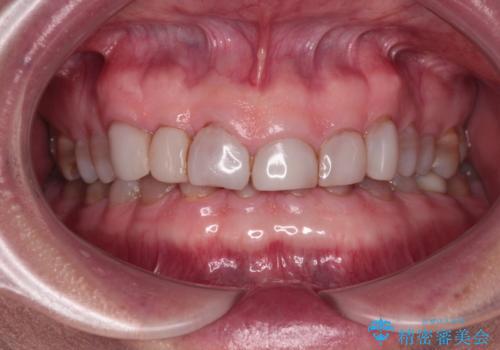

- 前歯の変色や欠損による隙間を気にして来院された患者様です。

上顎前歯は樹脂による変色を覆い隠す処置が行われていましたが、汚れが溜まりやすく厚みも増している状態でした。